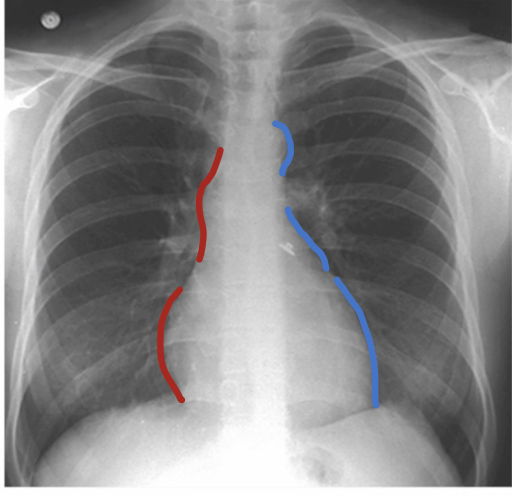

What mainly forms the right mediastinal border?

Superior vena cava

What are the three major bumps on the left mediastinal border?

Aortic arch or knob

Left atrial appendage

Left ventricle